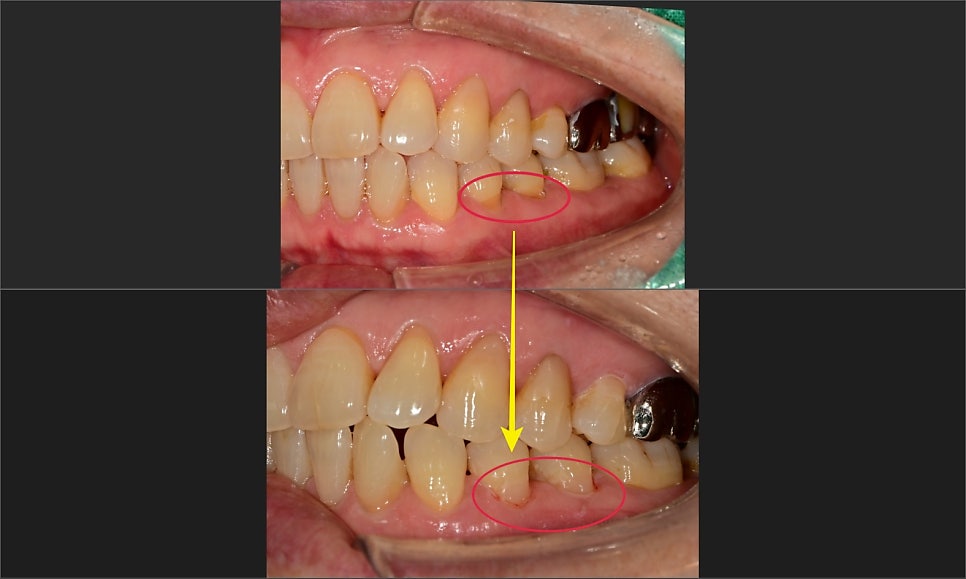

이런 경우는 아래 사진과 같이 그 부분만 간단하게 덮어주면 신경으로의 자극전달이 막혀

시린 증상은 바로 없어지게 됩니다.

어느 날 사진에 표시된 오른쪽 위가 찬물에 매우 시리다고 하셨습니다.